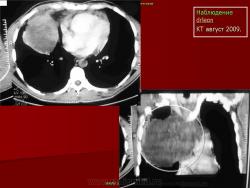

НАБЛЮДЕНИЯ КОЛЛЕГ

1.

2.